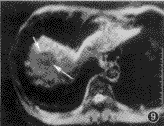

图8~10 男,59岁,乙型肝炎,肝硬化不典型腺瘤样增生结节癌变。图8为true-FISP T2WI,右肝近膈顶区见一略低信号病灶;图9为IR-EPI-ld T2WI,低信号病灶(长箭头)内见一略高信号结节(短箭头);图10为动态增强扫描动脉期,整个病灶强化不明显(长箭头),病灶内见一明显强化结节(短箭头)。手术病理证实为肝硬化不典型腺瘤样增生结节癌变